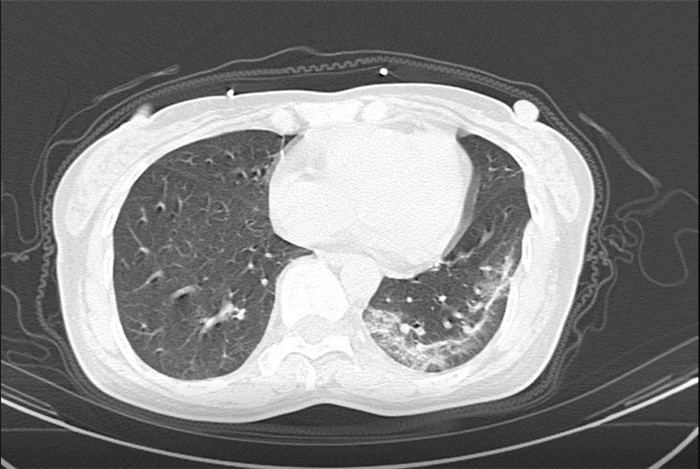

武漢大學中南醫(yī)院影像科副主任張笑春教授發(fā)現(xiàn),目前武漢市家庭聚集性發(fā)病較多,而且大多起病隱匿,一次甚至多次核酸陰性,無任何臨床癥狀,CT檢查卻已顯示為病毒性肺炎特征。

為了盡快篩查新型冠狀病毒肺炎患者,醫(yī)院會選擇影像診斷作為早期發(fā)現(xiàn)新型冠狀病毒感染的肺炎的重要一環(huán)。

CT為當前首選篩查與診斷的主要影像學手段,胸部CT的病毒性肺炎檢出率高。

方舟CT(CT Ark)可以滿足全面的臨床功能,配置16層、32層、64層、128層CT,實現(xiàn)了低劑量掃描要求,配合NDI微劑量迭代技術,智能毫安調控技術,使各種場合下、各部位低劑量掃描得以實現(xiàn);超高分辨率CT病灶靶掃描,使病灶的密度顯示更加精確,能夠顯示病灶內輕度的密度變化,有利于小病灶的密度定量分析和及時診斷。